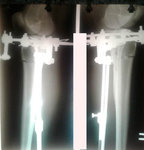

Рентген в 60 дней

Вложения